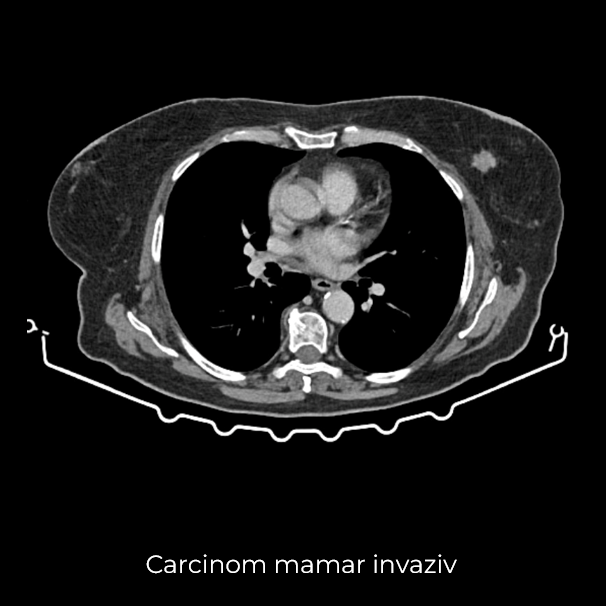

Uneori, o durere aparent banală ascunde în spate o realitate medicală mult mai serioasă. Așa s-a întâmplat și în cazul unei paciente de 63 de ani, care a ajuns la spital pentru dureri pelvine persistente. Investigația CT a schimbat însă complet perspectiva: au fost descoperite trei formațiuni tumorale în zone diferite ale corpului – o tumoră mamară stângă (carcinom mamar invaziv biopsiat), o tumoră pelvi-abdominală voluminoasă (tumoră ovariană) și o formațiune la nivelul peretelui posterior gastric (leiomiom gastric biopsiat).